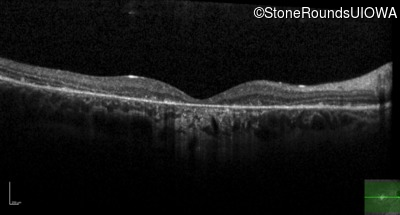

Age at visit: 26 years

OD OS

Age at visit: 27 years